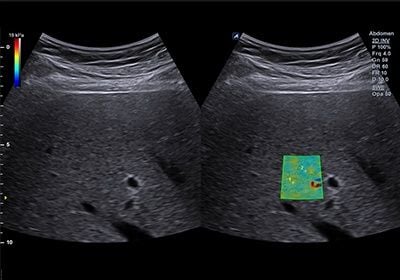

– 2D-SWE: siêu âm đàn hồi định lượng đa điểm. Kỹ thuật này có bản đồ đàn hồi định lượng độ cứng tại một vùng, ROI lớn và có hình ảnh B-mode hướng dẫn. Vì vậy đây là kỹ thuật có độ chính xác cao nhất trong các phương pháp. Có thể thực hiện với bệnh nhân béo phì, cổ chướng… Hình đàn hồi được tạo trong 1 bản đàn hồi định lượng, và ta thu được độ cứng trung bình của các điểm ảnh. Kỹ thuật này chỉ cần đo 5 lần là đủ.

Kỹ thuật siêu âm đàn hồi mô gan SWE:

- Kỹ thuật đo

Bước 1: Đánh giá nhu mô trên siêu âm 2D, chọn vị trí đặt ROI ở HPT 7 hoặc 8, dưới bao gan 2 cm, hướng trục ROI vuông góc bề mặt gan

Bước 2: Ấn phím đo sau khi bảo bệnh nhân ngưng thở lại khi đang thở ra nửa chừng

Máy tự động cho kết quả độ cứng và vận tốc sóng biến dạng

Tiến hành 10 lần, lấy giá trị trung vị (median).

Chỉ số IQR/Median < 30%